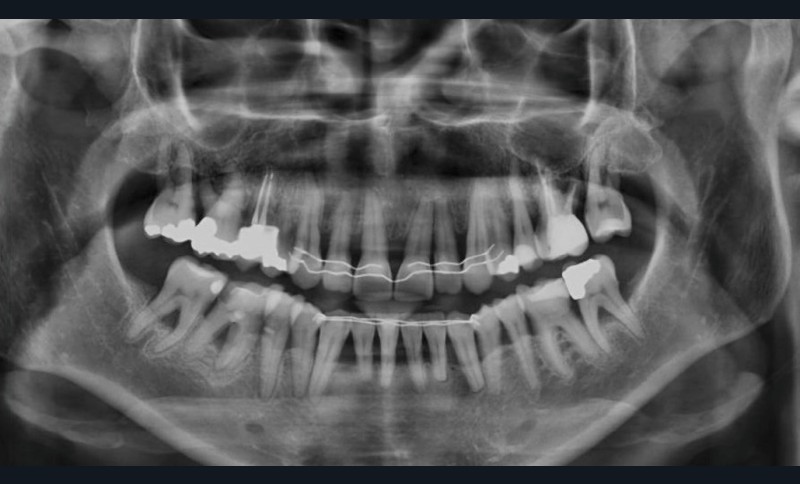

L’examen radiographique (fig. 3-5) nous indique une Classe I squelettique de Ballard (ANB 0°) sur un schéma facial à tendance hyperdivergent (FMA 28°). L’analyse céphalométrique confirme la vestibulo-version incisive (I/SN 111° ; IMPA 94°). La lyse osseuse est généralisée.